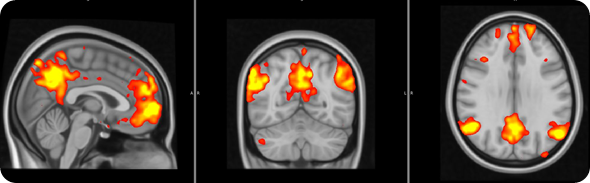

Fibro brain 2

We saw that the healthy subjects showed large brain responses, in many regions, when they were anticipating pain or relief. Some of these changes are likely to be due to the detection of ‘salient’ event. In other words, some of these responses may be non pain-specific and may simply reflect the fact that the subjects were detecting an ‘interesting event’.

However, other responses would seem to be even more interesting, and possibly pain specific: for instance the healthy volunteers activated a region called the ‘periaqueductal gray region’, which we know exerts a modulatory effect on the pain signals coming to the periphery (this is a region that if stimulated electrically can alleviate pain).

The healthy volunteers also showed that a region involved in the processing of ‘reward’/’punishment’, the so called ventral tegmental area (VTA), was activated during pain anticipation, and deactivated during relief anticipation.

FM patients exhibited reduced brain responses in response to visual cues for both pain anticipation as well as relief anticipation.

This reduced responsiveness was very widespread, and included the periaqueductal gray and the VTA.